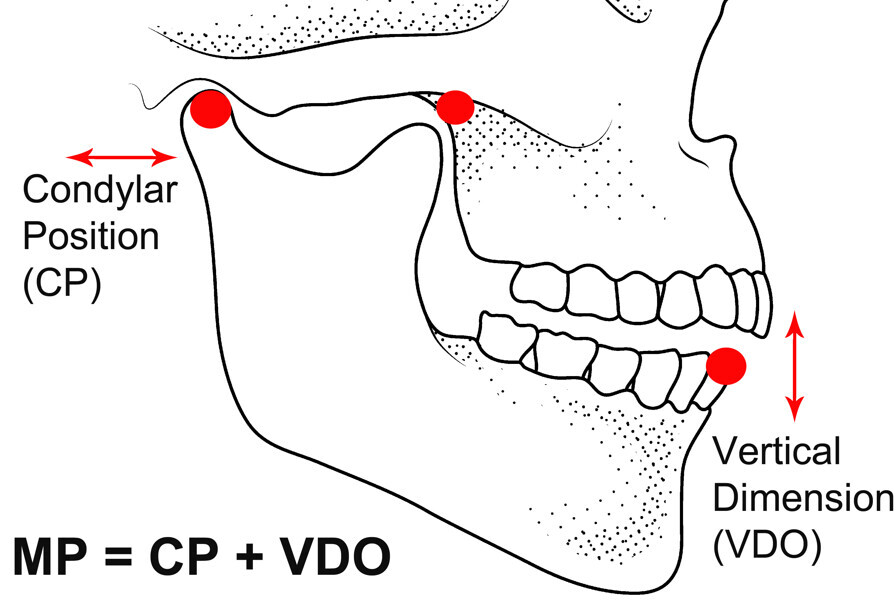

Fig. 4: Mandibular position defined as condylar position and vertical dimension of occlusion.